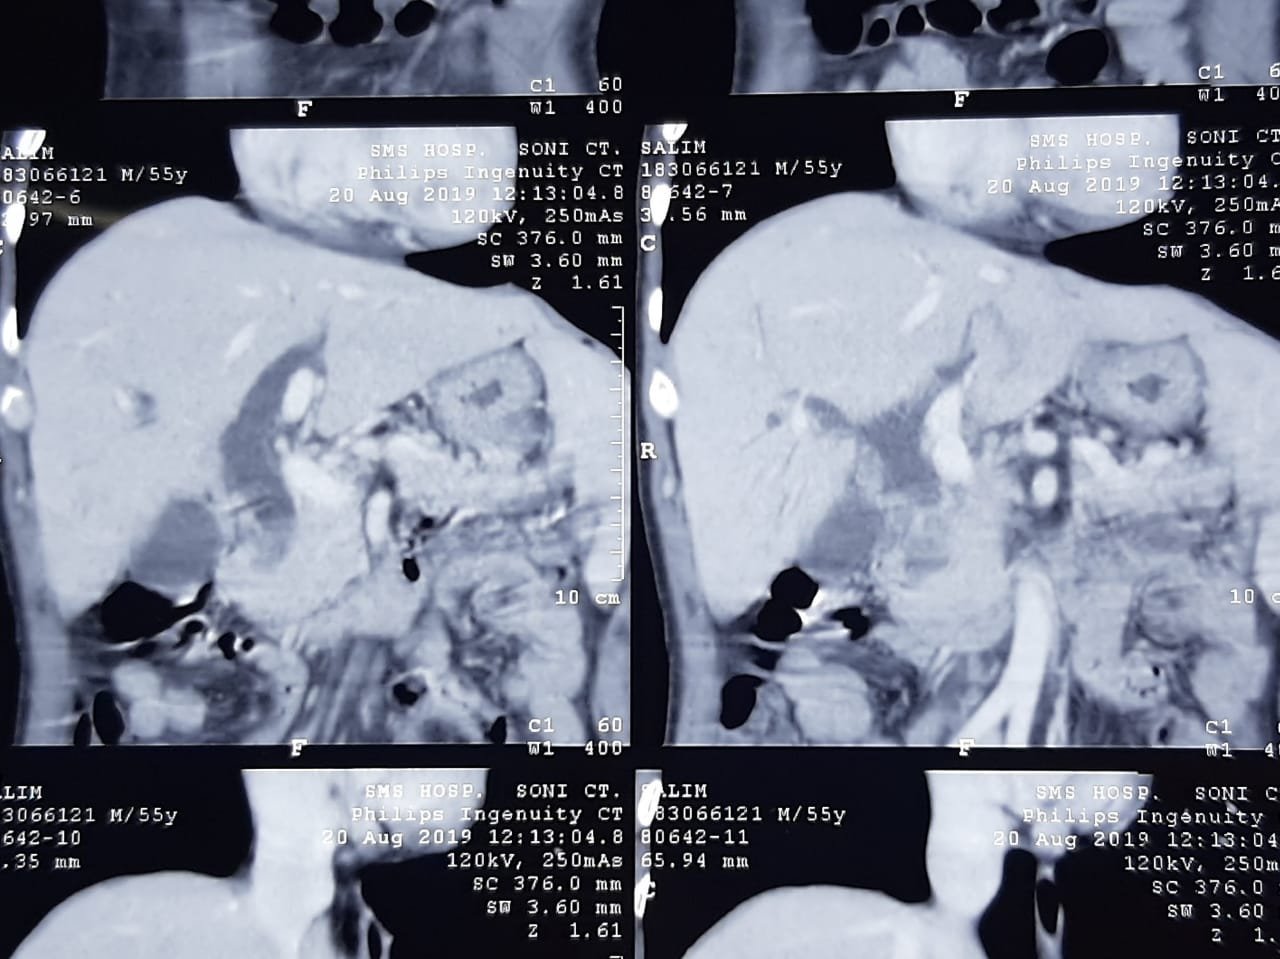

Blood tests such as amylase, lipase levels and imaging tests, such as computed tomography are usually required to make diagnosis.

Multidetector thin slice CT scan is helpful both in diagnosis, staging of disease and in treatment planning.